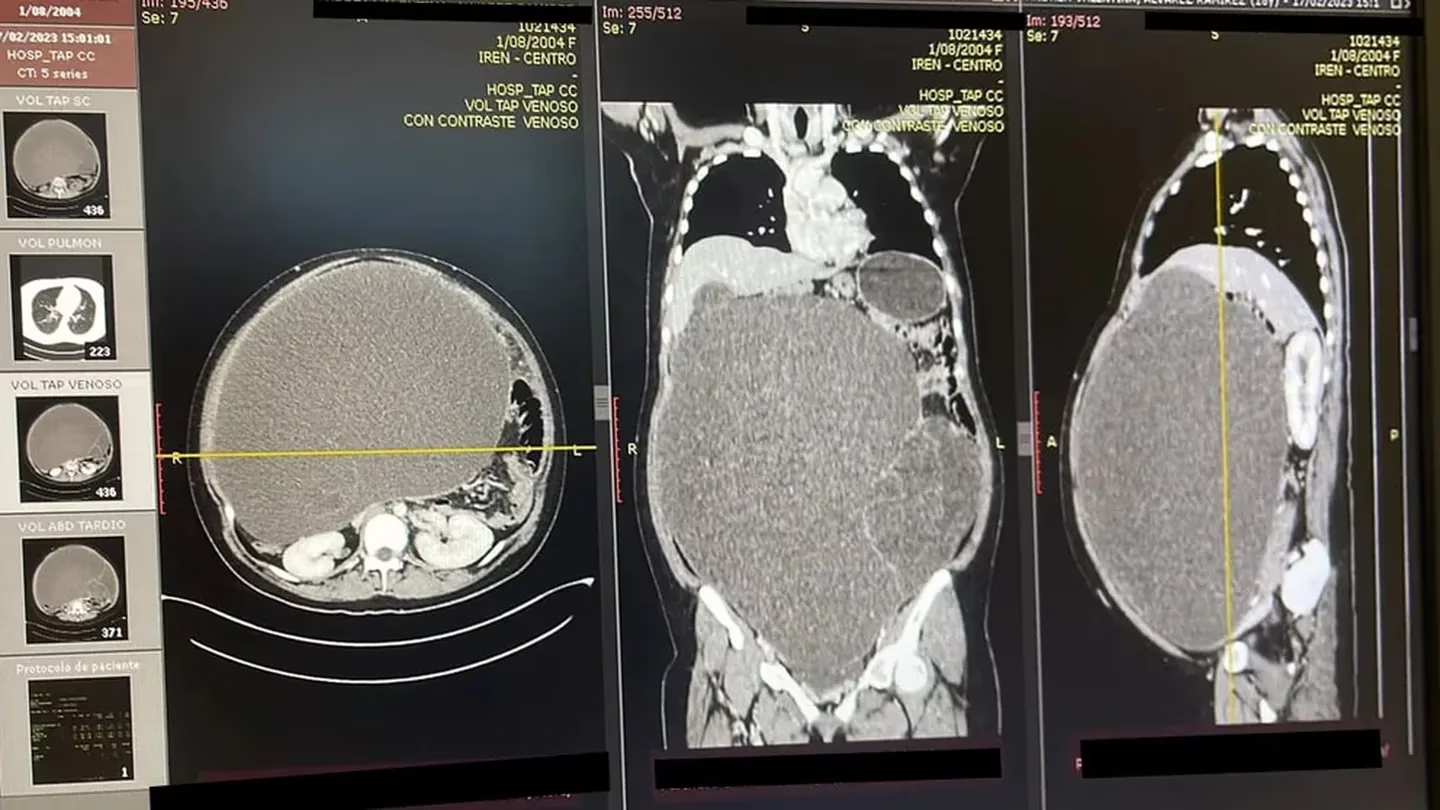

Andrea Álvarez, de 18 años, natural de la Selva Central de Perú, tenía alojado dentro de su abdomen un gigantesco tumor de un metro de largo y 20 kilos de peso, lo que comprometía seriamente su vida y tuvo que ser operada de urgencia.

El ministerio de Salud (Minsa) de Perú informó que médicos especialistas de la región Junín extirparon la tumoración de grandes dimensiones. Su familia había pensado que lo abultado de su barriga era por sobrepeso. El tamaño del abdomen era similar al de una persona embarazada de gemelos.

“Con éxito, se extrajo la tumoración abdominopélvica gigante con áreas quísticas y sólidas y se envió una muestra a estudios patológicos”, refirió el experto.